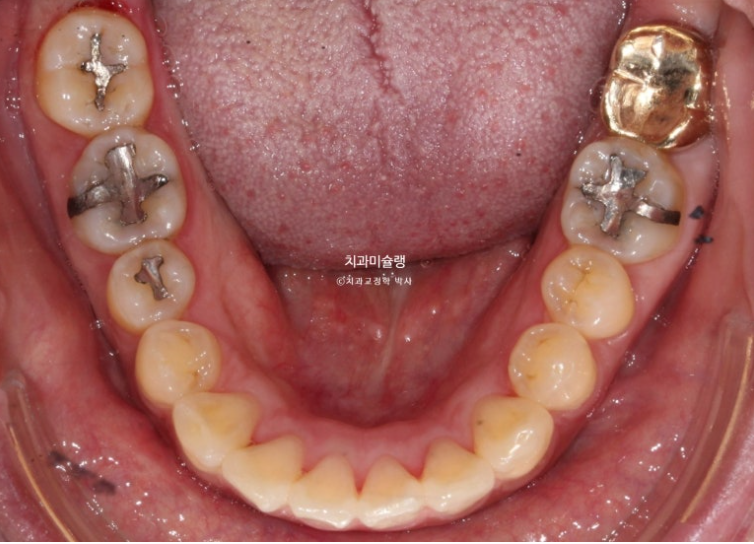

This patient was referred to us for orthodontic treatment three years ago.

You can see midline discrepancy and deep overbite.

The upper front teeth protrude forward.

According to the skeletal analysis, the patient has a recessed chin, meaning the lower jaw is smaller than the upper jaw.

The treatment plan was to extract only two upper premolars and use the wisdom tooth space in the lower jaw to move the teeth backward without extraction.

The patient chose Clippy-C, and treatment began.